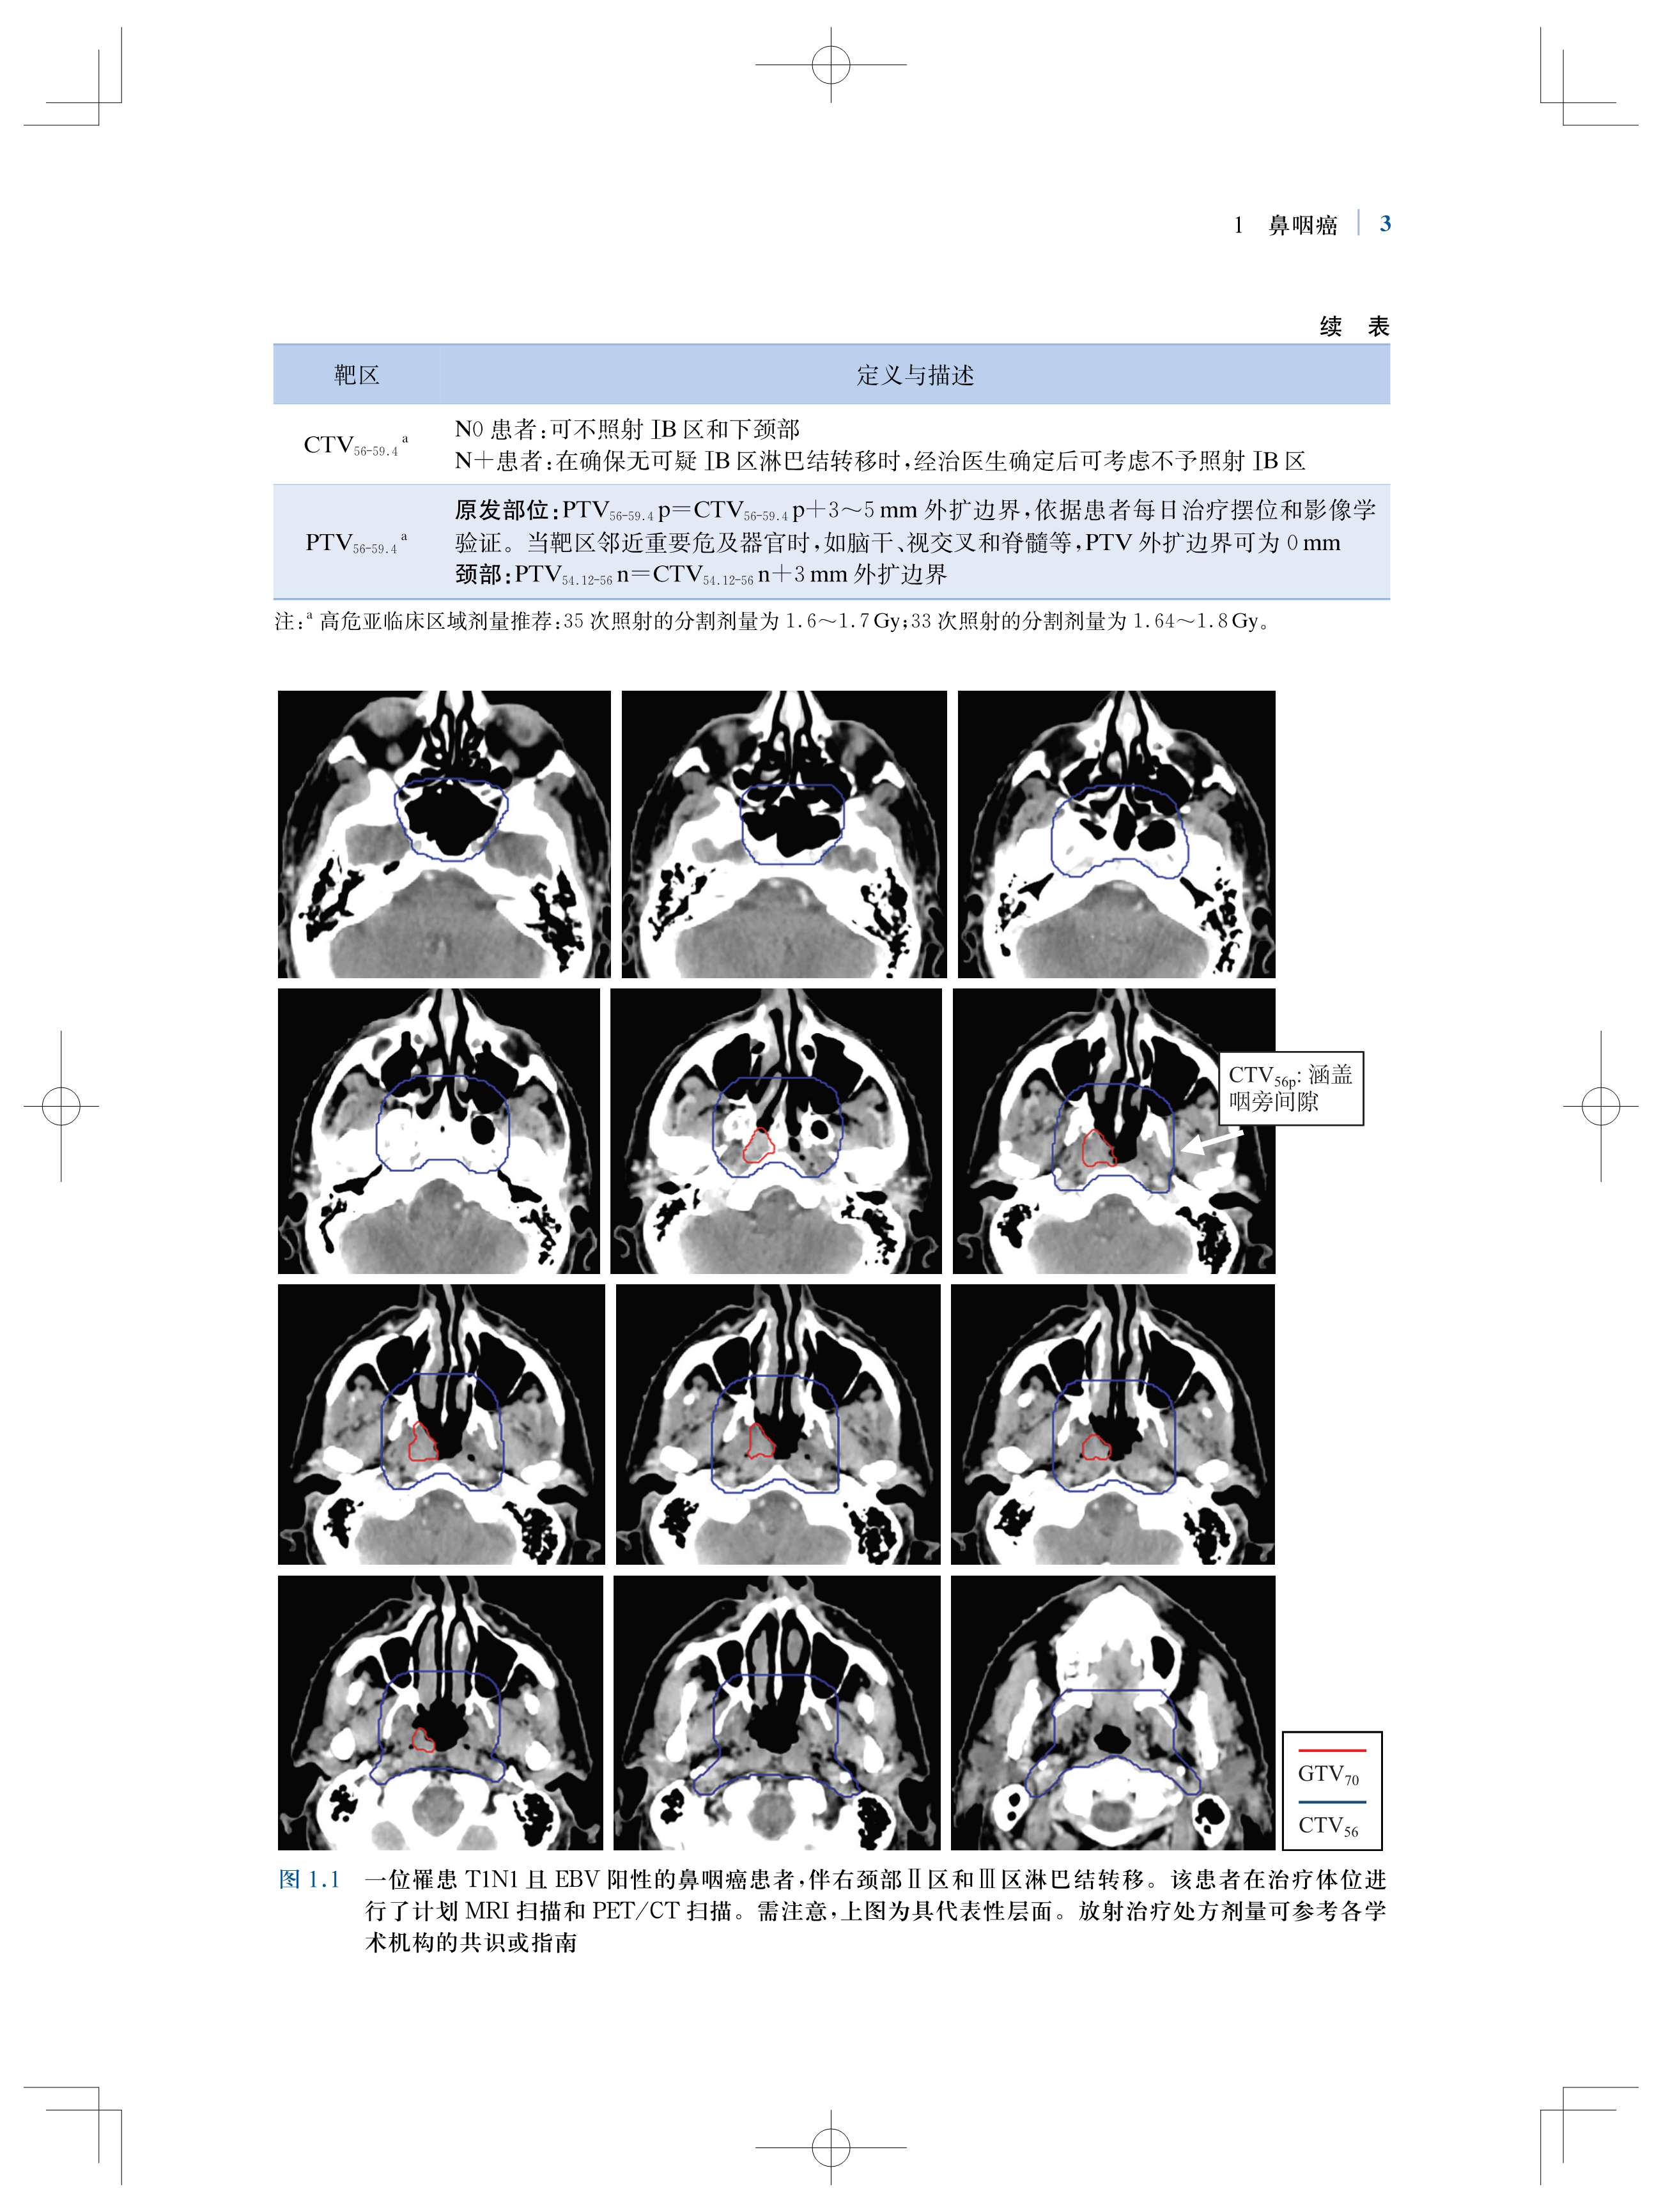

书名:肿瘤放射治疗靶区勾画与射野设置:适形及调强放射治疗实用指南(原著第2版)